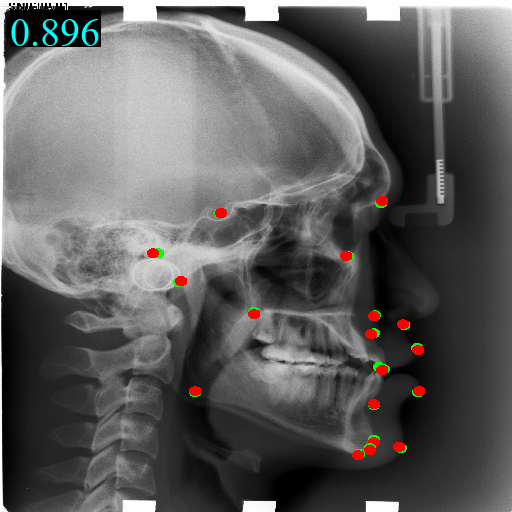

We take Model (f) which combines the above components as the final model. Model (f) using domain-adaptive transformer block and guidance network, beats any other models on all metrics by a huge gap. The predicted landmarks and heatmaps are exemplified in Figure 2.

Figure 2: Visualization examples of guidance heatmap Y~gsubscript~𝑌𝑔\tilde{Y}_{g}, fine heatmap Y~fsubscript~𝑌𝑓\tilde{Y}_{f}, output heatmap Y~~𝑌\tilde{Y} and images along with landmarks from four domains on head, hand, chest, and pelvis. The red points \bullet are predicted landmarks while the green points \bullet are annotated landmarks. The MRE value is on the top left corner of the image.